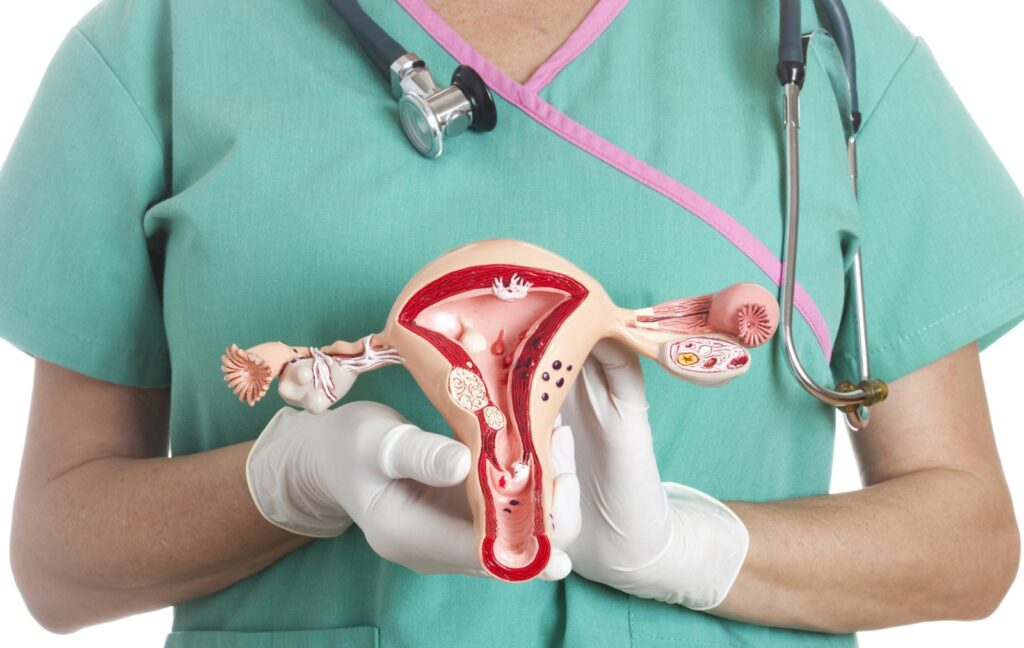

Detección de Diabetes Gestacional en el Consultorio:

Actualmente, una mujer embarazada debe acudir a un laboratorio para realizarse la prueba de HbA1c para detectar diabetes gestacional, lo que implica esperas y visitas adicionales. Con Hemoglinet, el ginecólogo puede realizar la prueba en el mismo consultorio, obteniendo resultados en minutos. Esto permite una detección temprana y una intervención oportuna, crucial para la salud de la madre y el bebé.